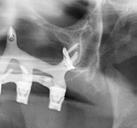

En la ortopantomografía se aprecia una dentición permanente a falta de la erupción de los 2os y 3 os molares, así como una asimetría ósea con rama y cóndilo mandibular izquierdo menos desarrollado (figura 9), causante de la asimetría facial descrita anteriormente.

El estudio cefalométrico (figura 10) revela una Clase II esquelética por hipoplasia mandibular, patrón braquifacial e incisivos superiores muy protruidos (14,9 mm) y

vestibulizados (52º), e inferiores lingualizados (16 º). El perfil es extremadamente convexo.